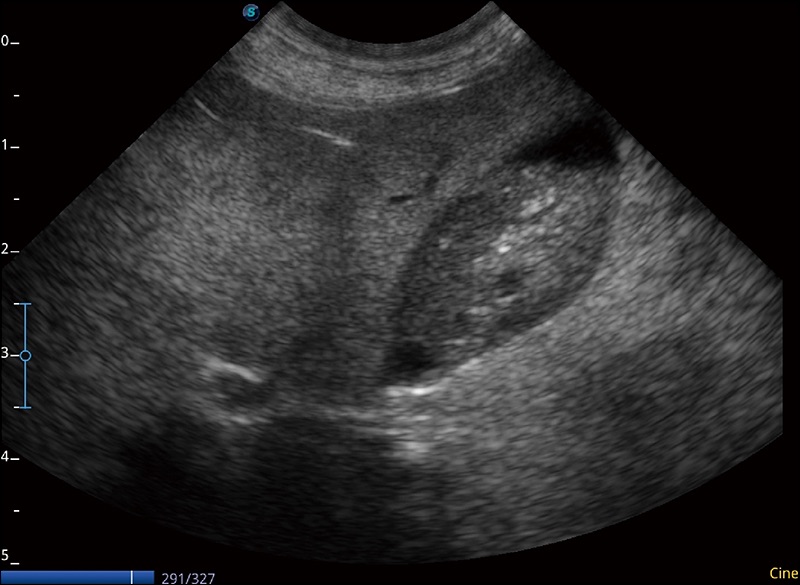

α1卓越的圖像質(zhì)量和便捷的工作流程,使每位寵物醫(yī)生都能輕松掃查。其全面的獸用應(yīng)用功能和緊湊型的結(jié)構(gòu)設(shè)計(jì),可以滿(mǎn)足動(dòng)物檢查的多種需要。專(zhuān)業(yè)的預(yù)設(shè)檢查模式和多領(lǐng)域測(cè)量軟件包有助于為不同類(lèi)型的動(dòng)物提供檢查, 讓寵物醫(yī)生能夠出色的完成工作。